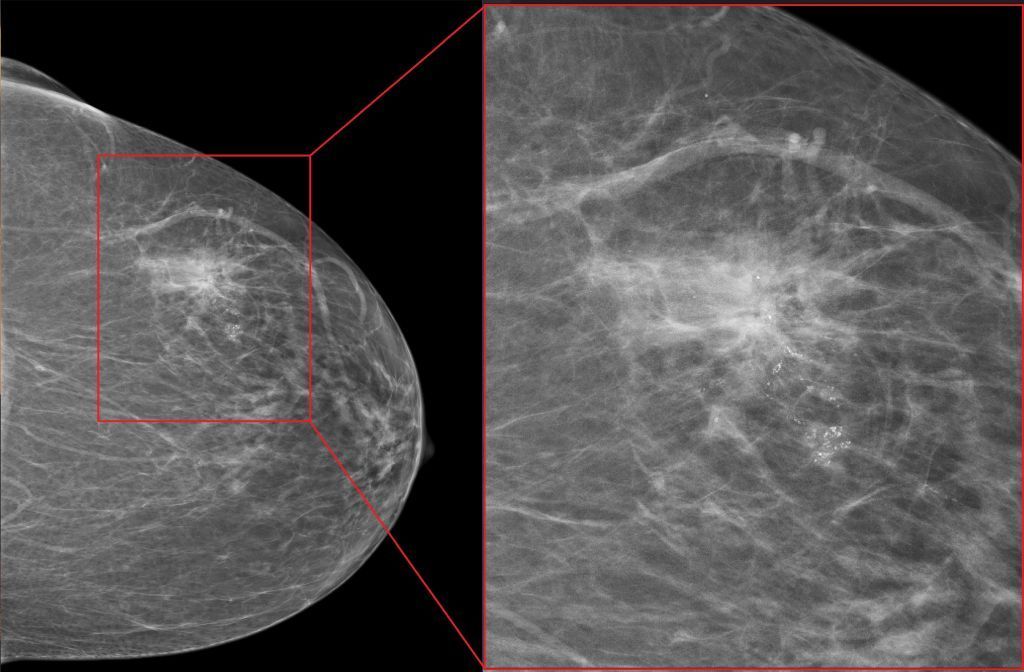

BI-RADS Klassifikation in der Mammographie

Die BI-RADS Klassifikation ist ein international anerkanntes System zur Beurteilung von Mammographiebefunden. BI-RADS steht für Breast Imaging Reporting and Data System und wurde vom American College of Radiology (ACR) entwickelt. Die Klassifikation dient dazu, die Befunde einheitlich zu beschreiben und die Wahrscheinlichkeit für das Vorliegen eines Mammakarzinoms anzugeben. Die BI-RADS Klassifikation wird in Deutschland Befundkategorie genannt und umfasst sechs Kategorien, die von 0 bis 5 nummeriert sind:

- BI-RADS 4 / Befundkategorie 4: Verdächtig. Es gibt Veränderungen in der Brust, die in 2-95% der Fälle bösartig sind, und eine Gewebeentnahme (Biopsie) zur histologischen Abklärung empfohlen wird.

- BI-RADS 5 / Befundkategorie 5: Hochgradig verdächtig. Es gibt Veränderungen in der Brust, die in mehr als 95% der Fälle bösartig sind, und eine Biopsie dringend erforderlich ist.